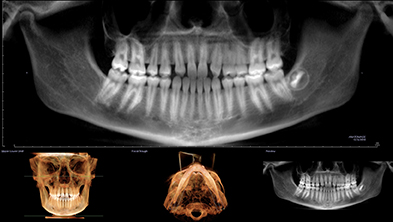

Radiografía 3D con agenesia de laterales